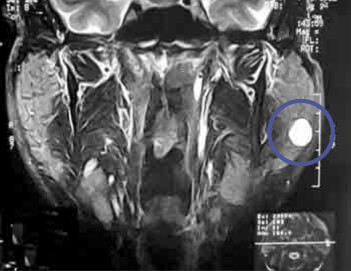

Speicheldrüse

Speicheldrüsen können durch die Bildung von Speichelsteinen, Entzündungen oder Tumoren Schwellungen verursachen.

Die Veränderungen werden durch verschiedene Untersuchungsmethoden erfasst. Je nach vorliegender Diagnose erfolgt eine medikamentöse oder chirurgische Therapie.